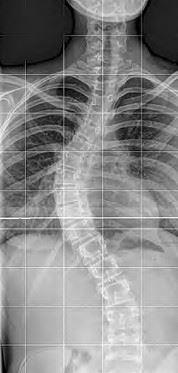

dionysBEWEGT - Dionys Schwery | Röntgenaufnahme einer skoliotischen Wirbelsäule

Röntgenaufnahme einer skoliotischen Wirbelsäule

Unter einer Skoliose versteht man eine seitliche Abweichung der Wirbelsäule von der Längsachse mit Verdrehungen der Wirbelkörper um die Längsachse. Es besteht ebenso die Möglichkeit, dass es zu Verschiebungen der Wirbelkörper gegeneinander kommt. Eine Skoliose kann mit strukturellen Verformungen der Wirbelkörper einhergehen. Die skoliotische Wirbelsäule bildet dabei in der Regel mehrere, einander gegenläufige seitliche Krümmungen, welche sich kompensieren, um das Körpergleichgewicht möglichst aufrechtzuerhalten. Typisch für die Skoliose ist das asymmetrische Körperbild mit einseitigem Schulterhochstand und Rippenbuckel.

Es wird zwischen funktionellen und strukturellen Skoliosen unterschieden, wobei bei strukturellen Skoliosen einzelne oder mehrerer Wirbelkörper Deformationen aufweisen. Der Schweregrad einer Skoliose wird auf Grund der seitlichen Abweichungen resp. deren Winkel beurteilt.